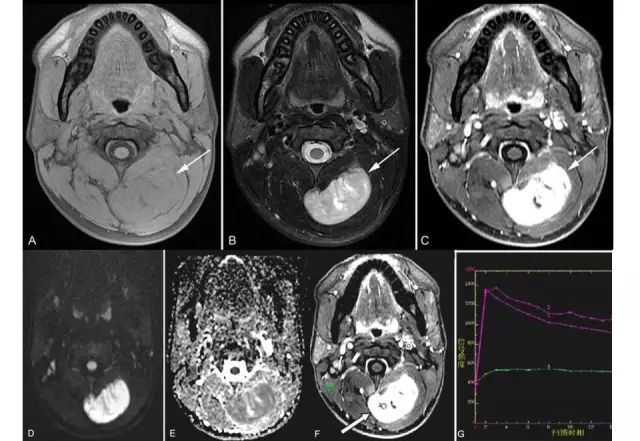

肿瘤在MRI上平扫表现为类圆形或分叶状肿块,T1WI信号多与肌肉相似,肿瘤合并出血时可出现小斑片状高信号区。少数因瘤内广泛的出血,整个肿瘤可呈高信号。T2WI上信号多不均匀,肿瘤内常出现高、等、低三种信号混合存在的征象,有学者称之“三信号征”(也有学者称之“三重信号征”或“三联征”)(图9、图10),是滑膜肉瘤MRI较为特征性征象之一。T2WI抑脂序列上滑膜肉瘤可呈多个大小近似的卵石状结节,其间存在低信号间隔,似铺路石状,称之为“铺路石征”(也有学者称之“卵石征”)(图11),也是滑膜肉瘤MRI较为特征性征象之一。部分病例(15%~25%)可出现液-液平面,为非特异性表现。常规MR增强扫描,肿瘤呈片絮状明显不均匀强化,分隔可呈明显强化(图11)。

磁共振功能成像技术在滑膜肉瘤的应用价值也较大。DCE-MRI上肿瘤实质部分TIC可为缓慢上升型(图12)或速升下降型(图13)。DWI上肿瘤实质部分可呈高信号,相应ADC值较低,内见斑片状DWI低信号区,相应ADC值较高(图13)。